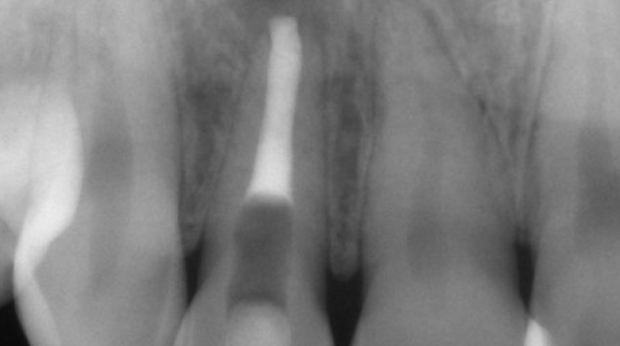

임플란트와 사랑니 발치는 외과적 시술로 잇몸을 절개하는 외과적 시술은

짧으면 짧을 수록 시술 후 붓기와 통증이 최소화됩니다.

치과의사 경력 14년차 구강외과 전문의가 빠르고 안전하게, 아프지 않게 수술해 드립니다.